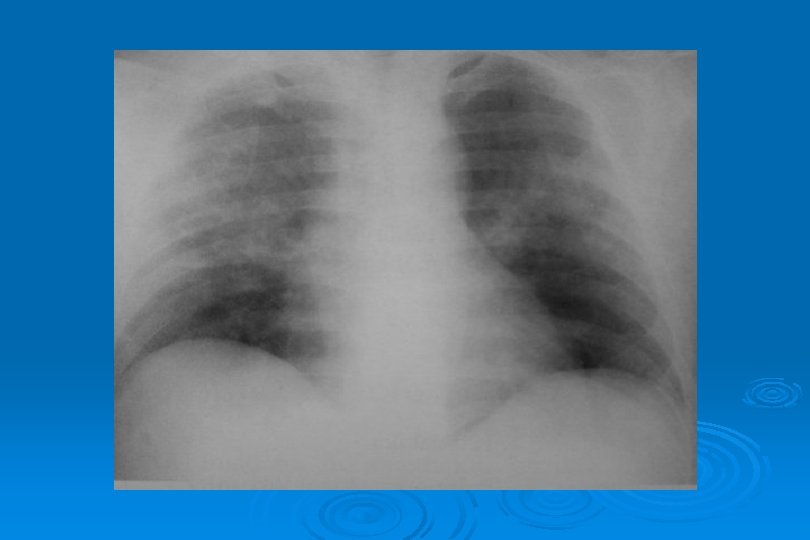

VİRAL AC ENFEKSİYONLARI Toplum kökenli pnömonilerin % 25’i Ø Yaygın ya da dağınık infiltrasyon şeklinde olan bakteriyel pnömonilerden ayrımı çok zordur Ø Klinik bilgi verilmediğinde olgularda pnömoninin viral veya bakteriyel olduğunu tahmin etmek güçtür Ø Lober genişleme, mikroabseler, kavitasyon ve ampiyem bakteriyel pnömoniyi destekler Ø

VİRAL AC ENFEKSİYONLARI Ø Viral pnömoni damlacık enfeksiyonudur Ø Trakeit, bronşit ve bronşiolit tablosu ortaya çıkar Ø AC grafisinde hilustan perifere yayılım, asiner gölgeler ve yer peribronşial kalınlaşmalar saptanır

VİRAL AC ENFEKSİYONLARI Ø Yan grafide retrokardiak alanlarda peribronşial kalınlaşma tren rayı şeklinde paralel, ince radyoopak çizgiler şeklinde daha kolay görülür Ø BT ve YRBT tanıda önemli tetkiklerdir

AKUT İNTERSTİSYEL PNÖMONİ Ø Bronş duvarında kalınlaşma Ø İnter ve intralobüler septalarda kalınlaşma sonucu hilustan perifere doğru yayılan retiküler patern Ø Yaygın milier görünüm

LOBÜLER VEYA ASİNER İNFİLTRASYONLAR Sekonder pulmoner lobüllerin opasifikasyonuna bağlı yamalı konsolidasyon görünümü (bronkopulmoner infiltrasyon) Ø Bronş etrafında 1 cm’den küçük asiner nodüller Ø Yaygın asiner nodüller suçiçeği pnömonisi için tipiktir Ø

LOKALİZE VEYA YAYGIN HEMORAJİK ÖDEM Lokal olduğunda radyolojik görünümü segmenter veya lober pnömoniye benzer Ø Yaygın hemorajik ödem akut ve şiddetli viral pnömonide hızla ortaya çıkan bir tablodur Ø Perihiller perifere doğru azalan yaygın alveoler opasiteler görülür Ø Bazen plevral effüzyon olaya eşlik eder Ø İnfluenza virüsü en sık nedendir Ø